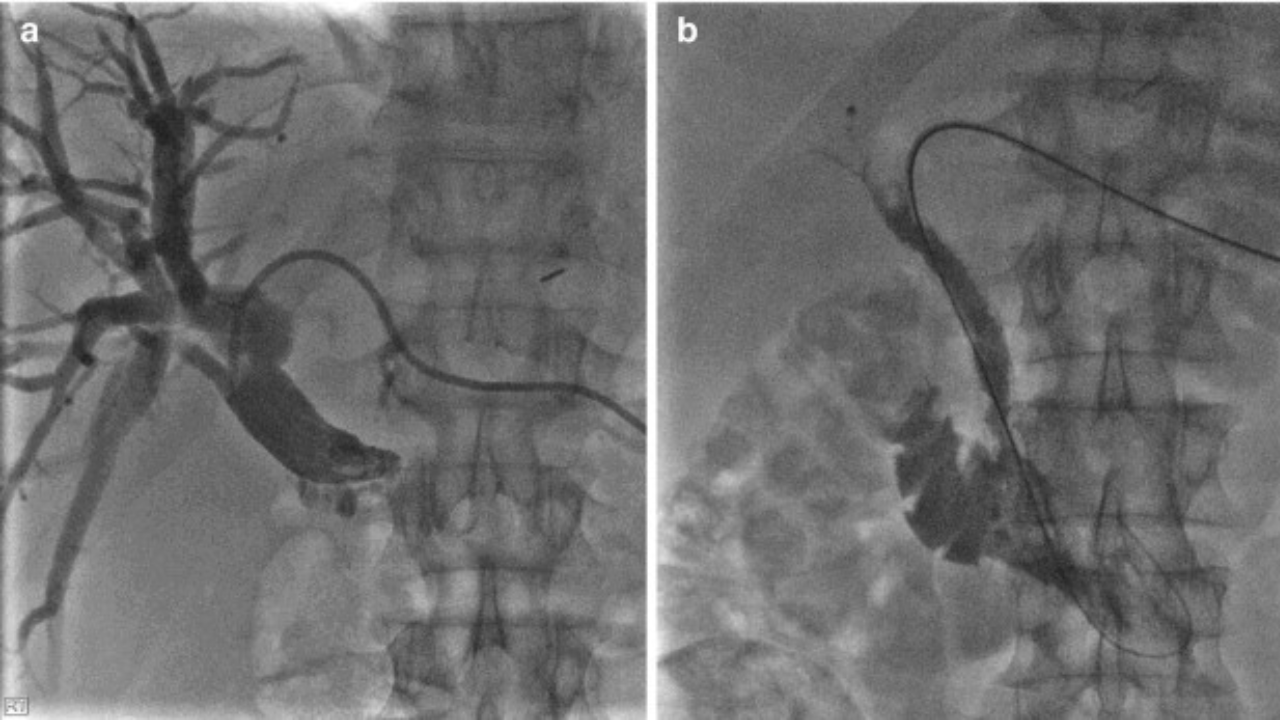

Percutaneous Transhepatic Cholangiography or PTC is an interventional procedure employed to diagnose as well as manage conditions affecting the bile duct. During the procedure, a thin needle is inserted through the skin into the liver and the contrast dye is passed into the bile ducts. This makes it possible to take pictures of the bile ducts to show the presence of obstruction, narrowing or any other problem.

PTC also has a therapeutic use for instance placing of stents to unlock the blockage, or for instance in cases of infections doing a bile drainage. It is an essential process in the diagnosis and treatment of different pathologies of the biliary tract in the patient.

Bile Duct Imaging: Endoscopy or detailed visualization in order to evaluate the existence of different pathologies such as blockage or strictures.

Stent Placement: To remove the blocks in the bile ducts and bring about normal functioning of bile.

Bile Drainage: Used in the treatment of severe infection, or obstruction leading to jaundice.